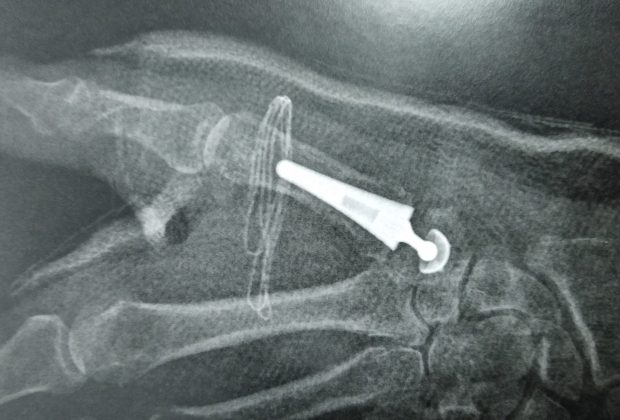

1er Prothèse pour arthrose du pouce à la Clinique Saint Charles

L’arthrose du pouce touche chaque année de plus en plus de femmes et d’hommes. Plus actifs dans leurs vies quotidiennes, cette arthrose devient aujourd’hui très ... -